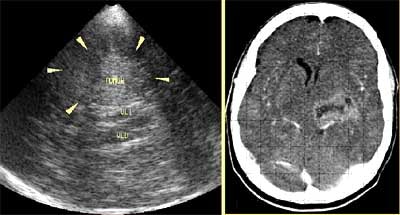

Brain tumors can be identified as echogenic masses surrounded by a hypoechoic halo. Heterogenous masses can be due to necrosis, cysts, or calcifications.

![]() |

| Cerebral teratoma in a 56-year-old male patient (left) with CT correlation (right). Images courtesy of Dr. Orlando Valls Pérez. |

"Intraoperatively, (transcranial Doppler sonography) guides the hand of the surgeon who is trying to separate normal from the abnormal tissue," during fine-needle aspirations and procedures to reduce cystic tumor volumes using aspiration techniques, Pérez said. "It helps to prevent hemorrhage and preserve more normal tissue."